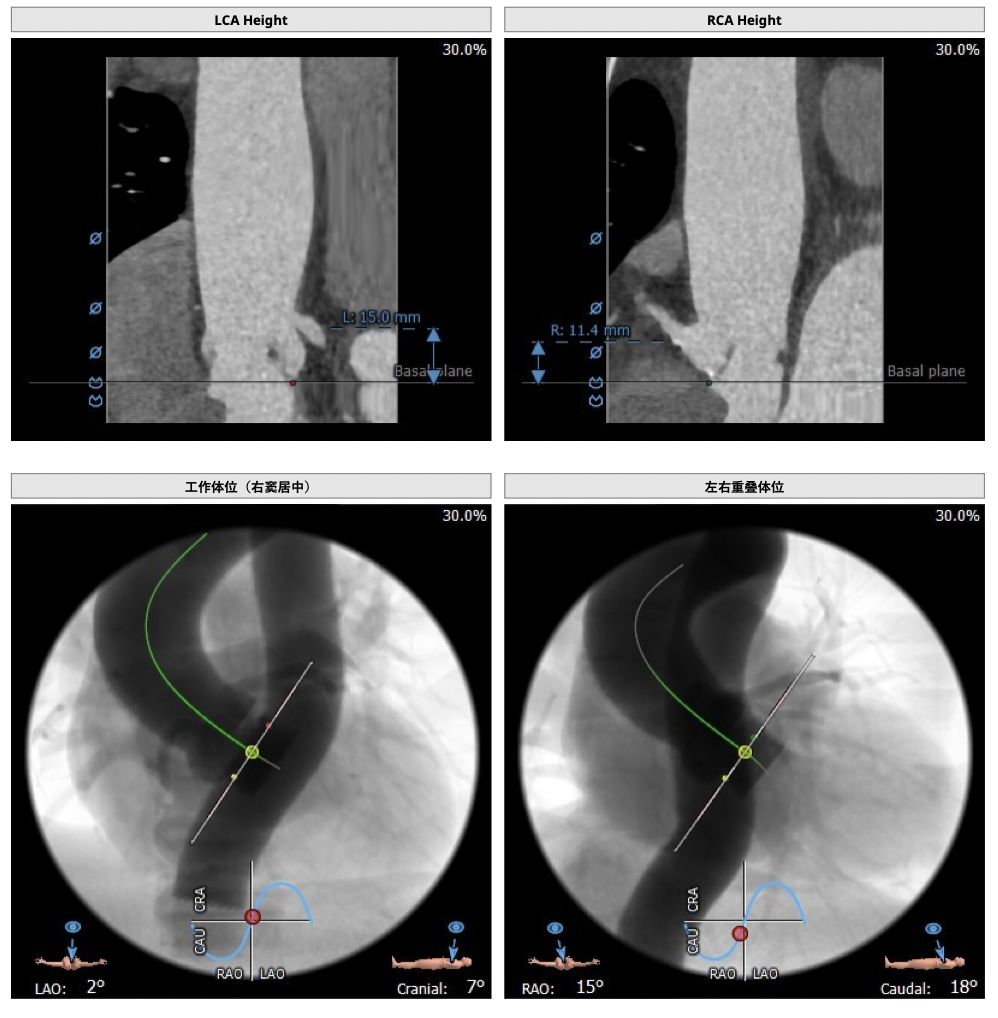

主动脉CT

难点分析:

*心脏角度为57°,横位心,输送器过瓣难度增加,瓣膜植入同轴性差,瓣膜释放更易移位,增加了操作的难度;

经分析研判,拟从右侧股动脉穿刺入路,使用20mm球囊预扩,采取downsize手术策略,选用L23号的VenusA-Valve瓣膜,因患者为横位心,瓣膜释放同轴性差,容易发生移位,故采用VenusA-Plus可回收输送系统确保瓣膜的稳定释放,瓣膜释放后结合造影和超声情况,决定是否后扩。

胶囊腔定位

瓣膜释放